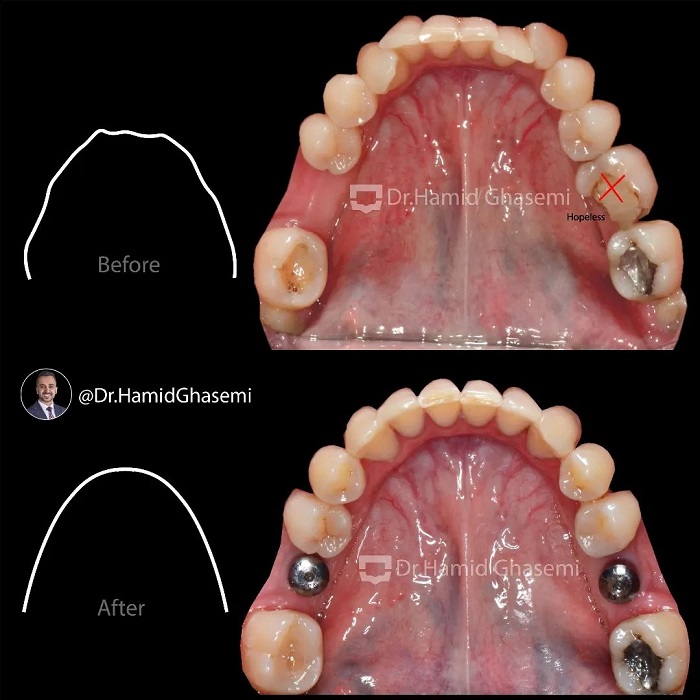

درمان ارتودنسی بدون جراحی در کیس با مشکل انحراف آرچ فکی و لبها ناشی از کشیدن یکطرفه دندان نیش فک بالا 👈👈 در این کیس به علت کمبود فضا و رویش دندان نیش خارج از قوس فکی دندانپزشک بدون مشاوره ارتودنسی اقدام به کشیدن یکطرفه دندان نیش سمت چپ بالا در سنین نوجوانی کردند و در نتیجه انحراف آرچ فکی و به دنبال آن انحراف لبها اتفاق افتاد. درمان در مدت ۲۴ ماه بدون هيچ گونه جراحی فک و جراحی بافت نرم با کشیدن یکطرفه دندان پرمولر دوم در سمت راست جهت چرخش آرچ فکی بالا به سمت راست انجام شد. دندان پرمولر اول سمت چپ جایگزین دندان نیش کشیده شده در سمت چپ شد. به تغییرات قابل توجه در بهبود قرینگی لبخند و لبها توجه کنید که به واسطه اصلاح آرچ فکی حاصل شد.

Non surgical orthodontic treatment of case with upper arch and lips asymmetry due to unilateral extraction of upper canine 👉👉 In this case due to lack of space and displaced upper left canine out of dental arch the dentist attempted to extract upper displaced canine without orthodontic consultation in adolescent and as a result upper arch and lips asymmetry occured. Treatment done for her within 24 months without any surgical procedures on jaws and lips by unilateral extraction of upper right 2nd premolar in order to shift upper arch to the right and then upper left 1st premolar substituted for missing canine on left side. Take note on significant Improvement of lips symmetry followed by correction of upper arch asymmetry